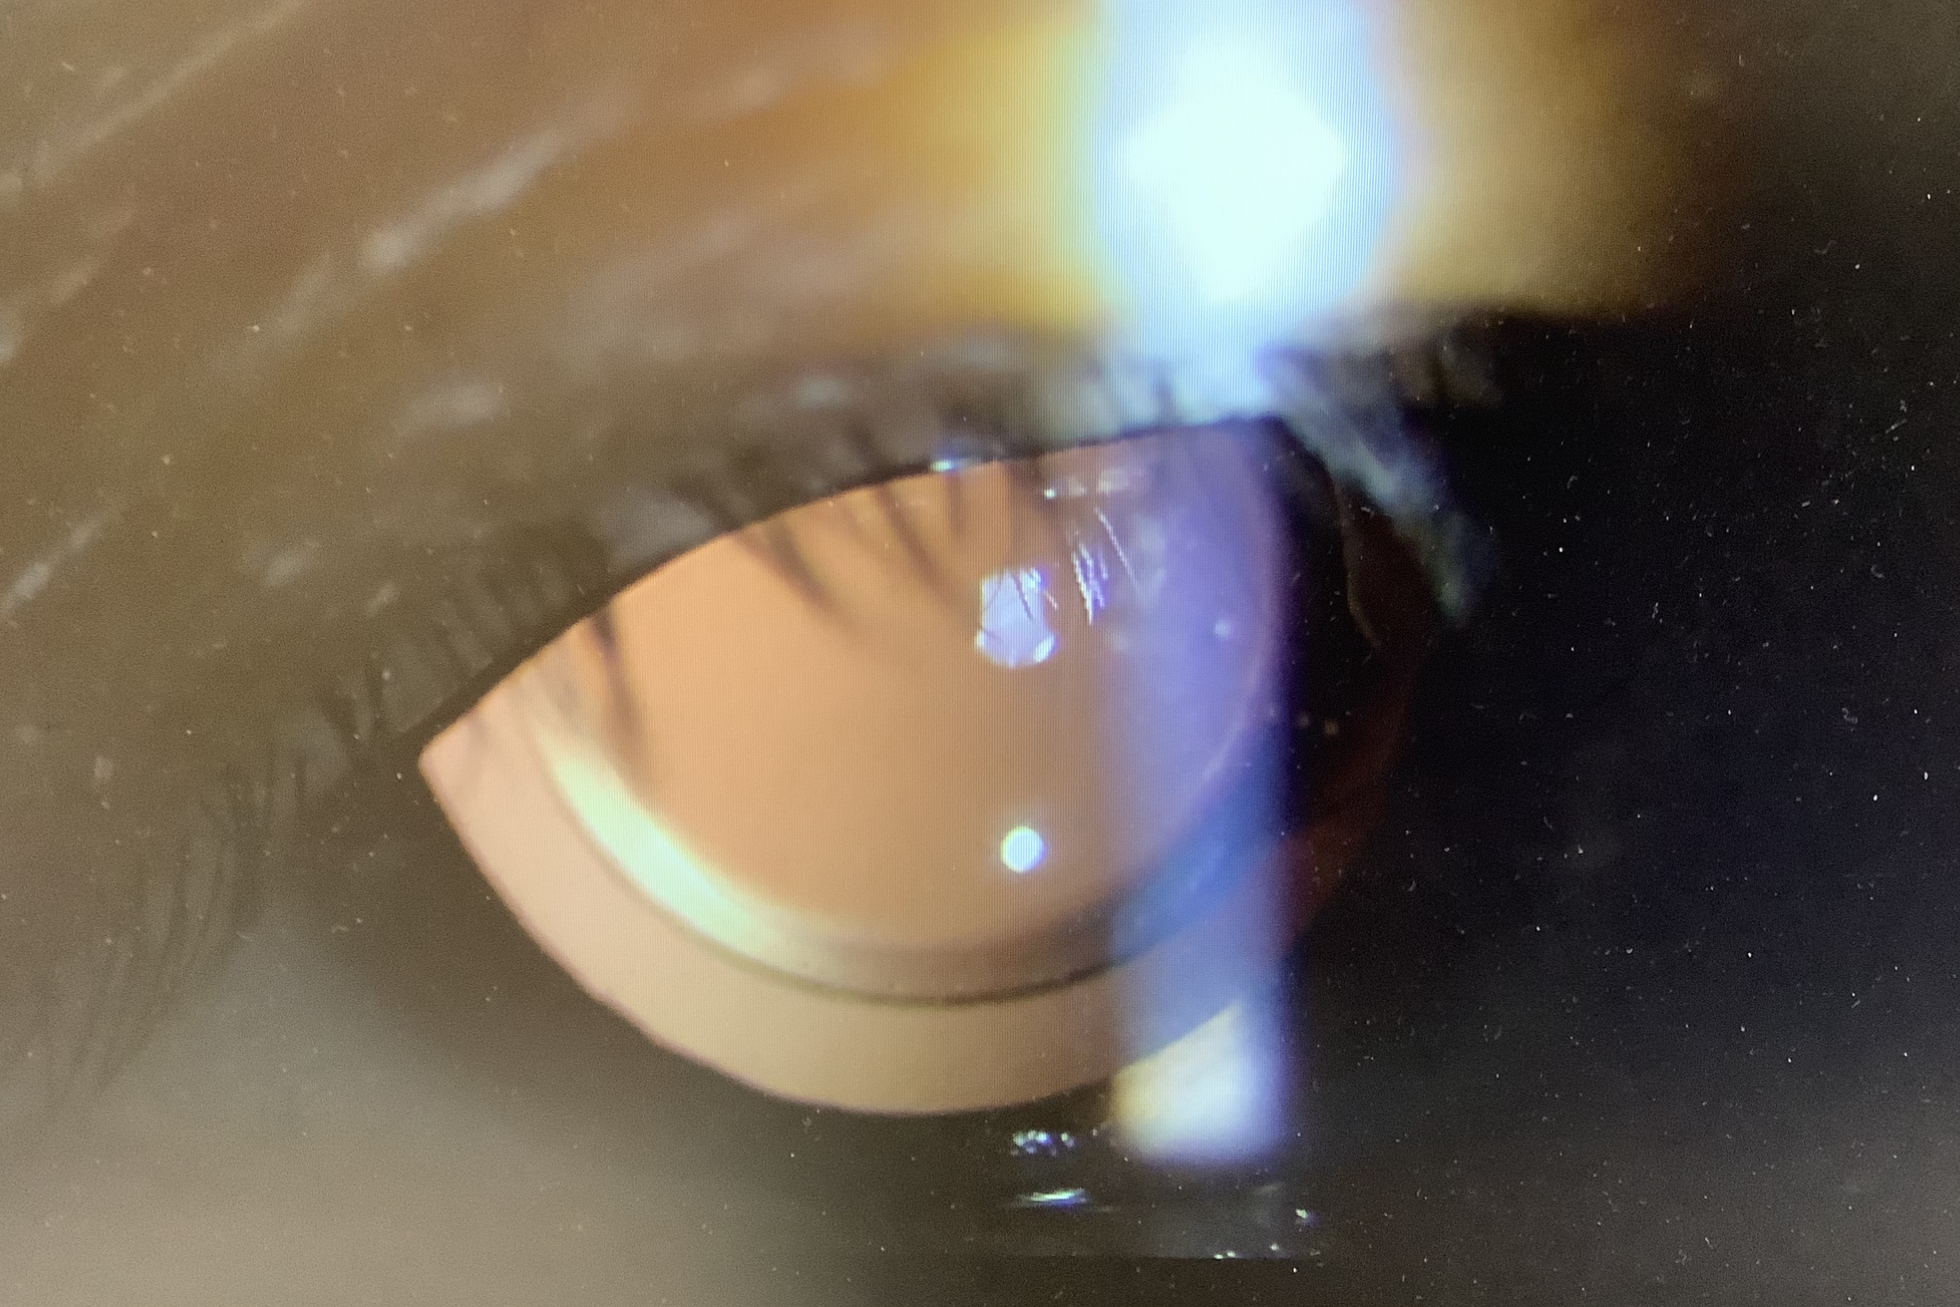

昨日、左眼の白内障の手術を受けていただいた70代の男性の方は、右-2.5D 左-4.5Dの近視の眼で、眼内レンズのピントは遠方に合わせ、今日の視力は裸眼でになりました。近視のある眼で眼内レンズを遠方に合わせると、片眼は眼鏡なしで遠方が見えるようになりますが、手術していない眼は遠くが見えにくい状態になります。眼鏡はどうしたらよいか聞かれることも多いのですが、今まで使っていた眼鏡はそのまま使えないことが多く、手術した方の眼を中心に裸眼で過ごすか、手術した方の眼の眼鏡のレンズを外して(眼鏡屋さんで外してくれます)、眼鏡をかけて過ごしていただくことになります。いずれにしても、ちょっと不便は感じてしまうと思いますが、もう片眼の手術までは少しご辛抱いただければと思います。また、両眼の手術の後は、近方が見えにくくなってしまいますから、老眼鏡(近用鏡)を使う必要が出てきます。老眼鏡の処方は、度数が落ち着く術後1〜2か月で作るとよいですが、どうしても早めに処方ご希望でしたら、作ってはいけないこともありませんし、とりあえずは、市販の安い老眼鏡を使うのでもよいかと思います。術後の眼鏡はどうしなければいけないということもないのですが、困り具合によって、考えていただければと思います。